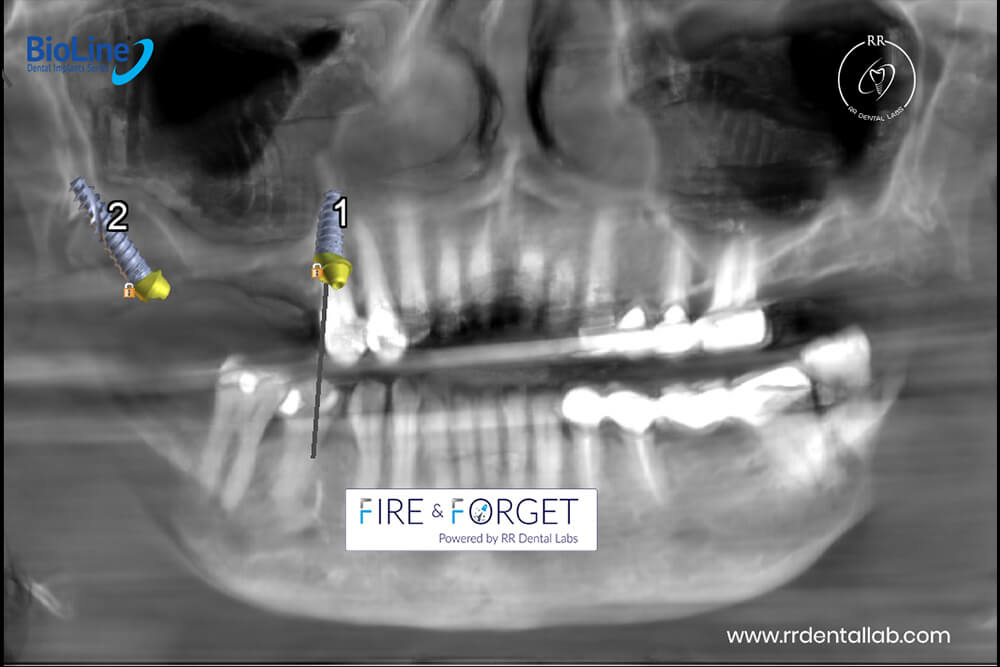

Case 73